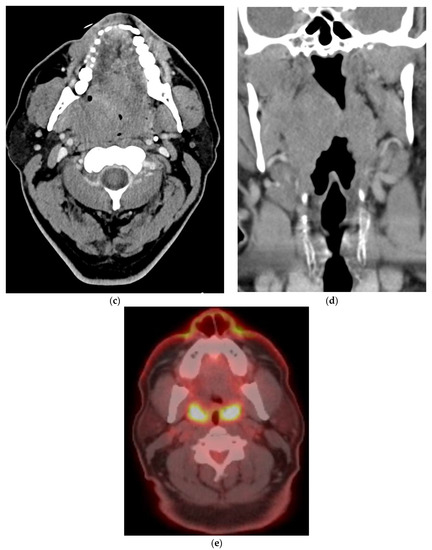

- Detection of occult primary lesions in patients presenting with large nodal metastatic masses without identifiable primary cancer on conventional imaging (CT/MRI) before EUA, biopsies, and tonsillectomy.

8.1. Initial Staging